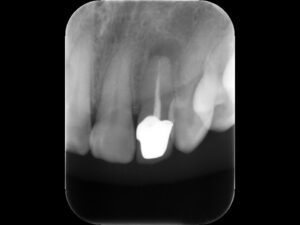

初診時レントゲン。根管充填がプアなため、根尖病巣を生じている。まずは再根管治療が必要と判断。たとえ高価な被せ物を被せても、根管治療に問題があると、いずれ再治療を行うか、いずれ抜歯になることに注意が必要。